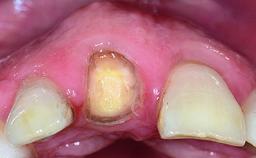

A healthy 37-year-old female patient was referred for a consultation on the replacement of missing tooth 21 with an implant-supported restoration. She stated that several years previously the tooth had been traumatically avulsed following a motor vehicle accident. The tooth was replaced with a three-unit fixed partial denture (FPD) immediately afterwards. Over time, she became disillusioned with the FPD and looked for a different option, including orthodontic therapy. She presented still in her orthodontic appliances, with the pontic sectioned free from the FPD but attached to the archwire. Her orthodontist felt that orthodontic treatment had been successfully completed, but nevertheless referred her before removing the appliances in case adjustments were necessary.